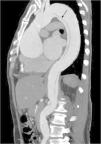

Caso de disección aórtica con sitio de reentrada y datos de hipoperfusión visceral. Paciente masculino de 64 años de edad con diagnóstico de disección aórtica; la flecha negra marca un sitio de reentrada a nivel de las renales, y el asterisco (*) muestra una disminución de la atenuación de la corteza renal izquierda al compararla con la contralateral.

Así mismo, los colgajos de disección pueden ser de diversa morfología, dentro de lo cual un dato importante a estudiar, sobre todo para la planeación del manejo terapéutico, es la cantidad de sitios de reentrada entre la luz falsa y la luz verdadera (fig. 3), ya que se ha visto que el número de reentradas puede asociarse a cambios en la movilidad del colgajo de disección, afectando el flujo intraluminal, que puede tener repercusiones hemodinámicas en el paciente11. En el presente estudio, el 50% de los casos no presentaron sitios de reentrada. El 18.8% tuvo un sitio de reentrada, mismo porcentaje obtenido en pacientes con 2 sitios de reentrada. No se observaron pacientes con 3 sitios de reentrada. Solo el 3.1% tuvo 4 sitios de reentrada, y el 9.4% de los pacientes tuvieron 5 o más sitios de reentrada. En el presente estudio no se encontró asociación significativa entre la mortalidad y los sitios de reentrada.